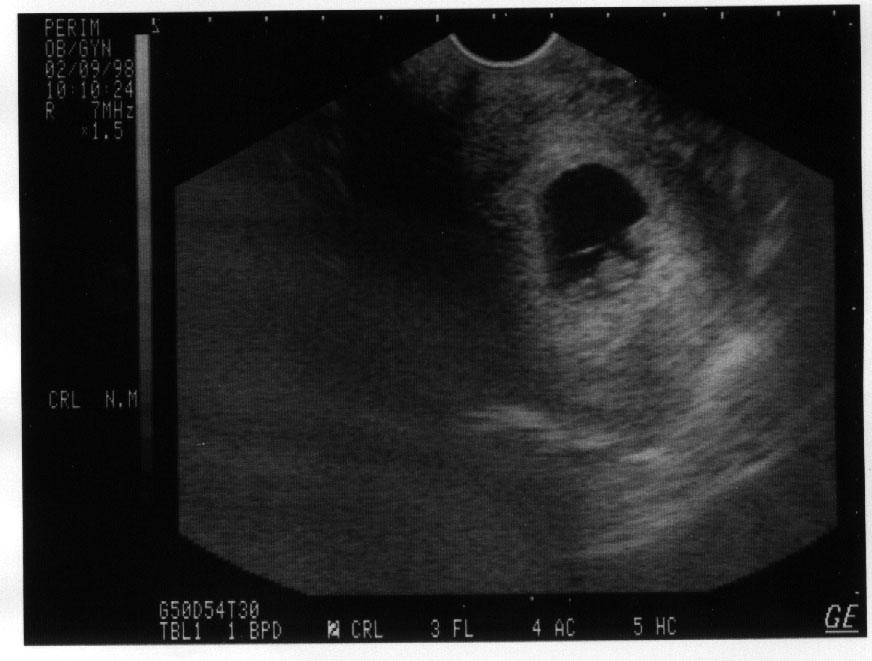

Sonogram

Sonogram of Cassandra in her second month.